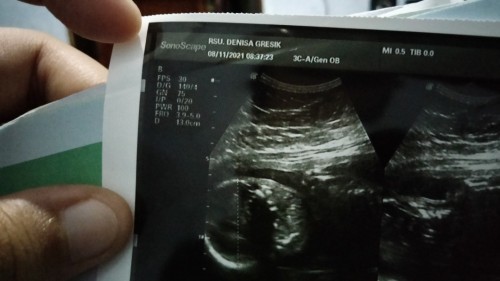

Ada yang bisa baca gak?? nyoba ke dokter lain ehh malah gk enak, penjelasan kurang dan kayak buru buru aja 🤦🏻♀️

Andai ada nggak mungkin saya tanya bun.. Kode usg ndak ada kayak gini, entah ini singkatan apa